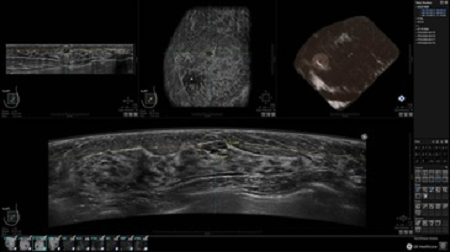

GE INVENIA ABUS – это современный УЗИ аппарат, который создан для точной и эффективной диагностики сканирования с высокой плотностью молочных желез. Выявляемость патологий раковых и предраковых стадий заболевания составляет 55%, что в конечном счете позволяет ставить врачу точные и своевременные диагнозы. Традиционные методы использования маммографии не показывают такой выявляемости, ограничиваясь лишь 3-38%.

УЗИ-аппарат GE INVENIA ABUS позволяет проводить максимально операторонезависимые процедуры, что значительно снижает риск неправильной постановки диагноза и сопутствующие издержки на обработку информации. Система готовит отчет в течение 3-х минут после сканирования, это безусловное преимущество по сравнению с обычным УЗИ сканером.

• Получение объемных 3D изображений с возможностью покадрового просмотра

• Отображение объемных 3D ультразвуковых изображений, которые состоят из традиционных поперечных и воссозданных коронарных и сагиттальных проекций

• Стандартизованная ориентация изображения: «толстый срез» в коронарной плоскости; поперечная; сагиттальная плоскость; радиальный и антирадиальный поворот изображения; просмотр исключительно области интереса

• 360 ° APC - отображение области по «любой точке компаса»